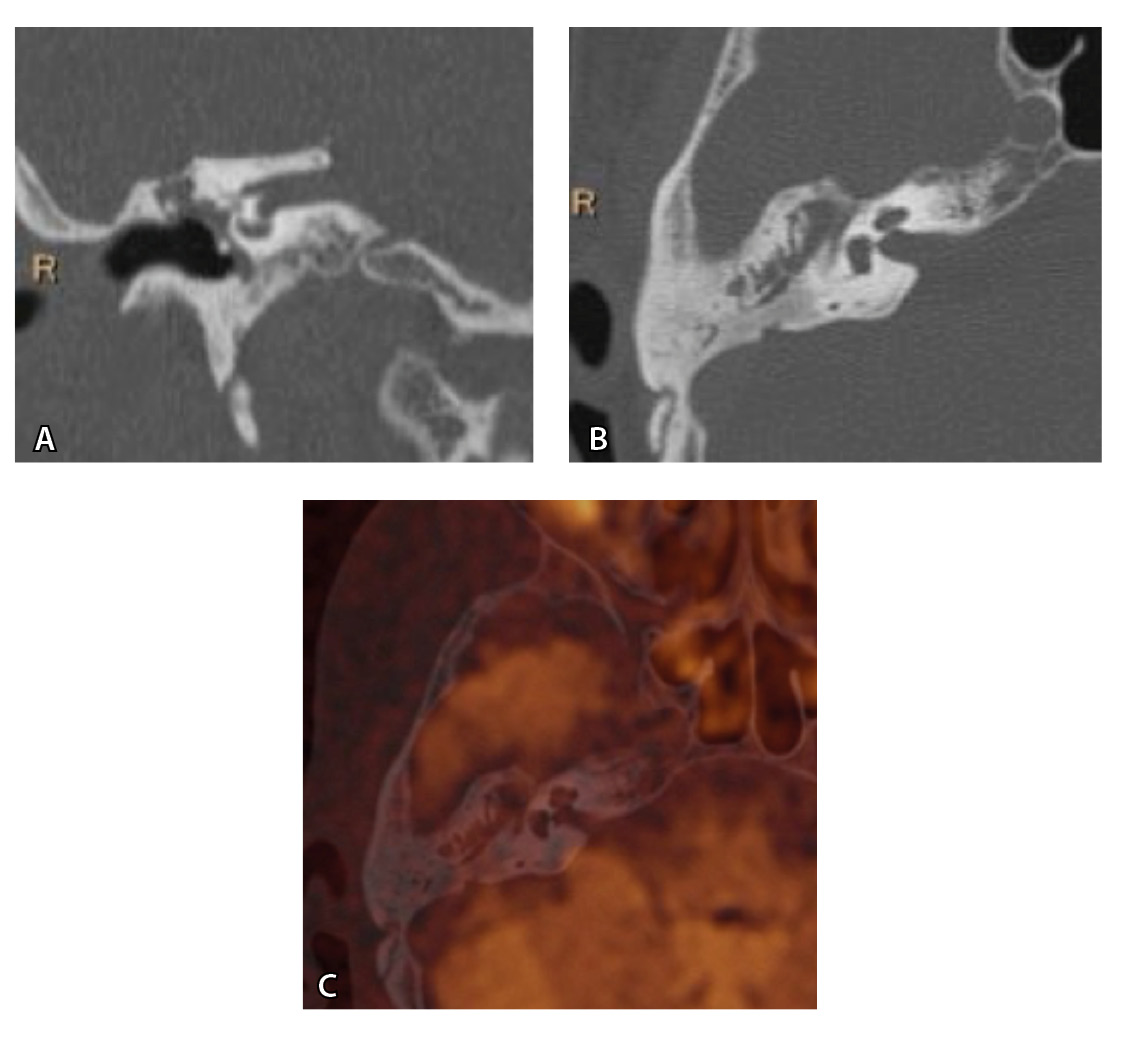

Рис. 3. Хронический правосторонний средний отит. По данным компьютерной томографии (А, Б) нет ремоделирования барабанной полости, деструкции и смещения косточек, скутум сохранен, данных за холестеатому нет. При магнитно-резонансной томографии (В, Г) у того же пациента выявлен очаг высокого магнитно-резонансного сигнала, который при слиянии локализовался в области пространства Пруссака. Заключение и интраоперационно – холестеатома пространства Пруссака

Рис. 4. При компьютерной томографии (КТ) визуализируются признаки хронического гнойного среднего отита справа. Наблюдаются латерализация косточек среднего уха и узурация их по имедиальной поверхности на уровне эпитимпанума (тело наковальни и головка молоточка) – классические КТ-признаки холестеатомы натянутой части барабанной перепонки (А, Б). Однако по данным магнитно-резонансной томографии (В) и в последующем при оперативном лечении холестеатома не подтверждена